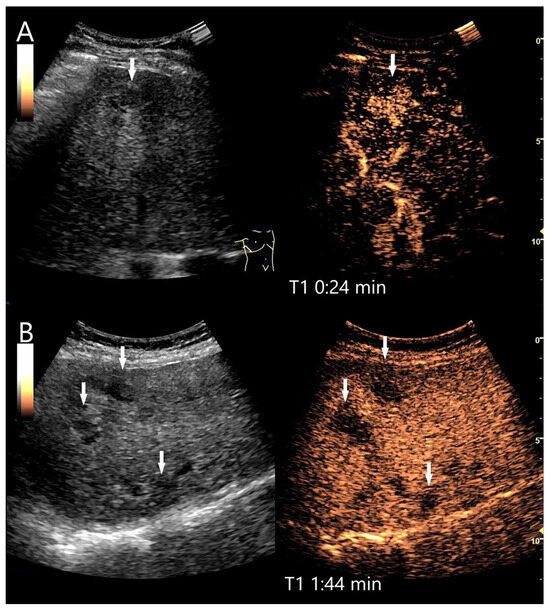

Figure 16.

IgG4-associated inflammatory pseudotumor. In a patient with elevated liver enzymes and alcohol abuse, B-mode US showed steatosis hepatis and a 55 × 20 mm irregular oval hypoechoic lesion (A). The central tubular structure was without flow evidence on CDI, and we interpreted this as a small bile duct branch. On CEUS, the lesion (arrows) was homogeneously hyperenhanced in the AP (B). In the PVP, a mild hypoenhancement developed (C), which became more pronounced in the LP (D).